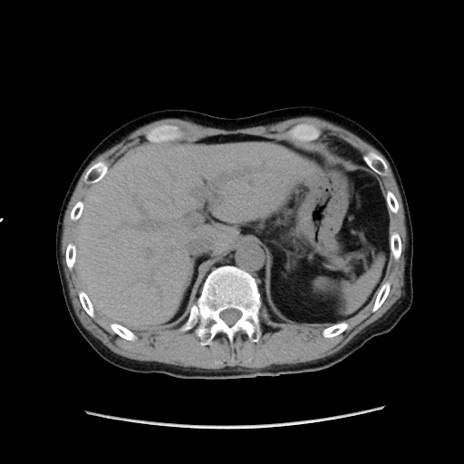

症例37(横断像)

【症例】40歳代 男性

【主訴】腹痛

【現病歴】4時間ほど前に電車に乗車中に臍部上より腹痛出現。徐々に増悪し起立困難となり、救急外来受診。生ものは数日食べていない。今朝お雑煮を食べた。

【身体所見】BT 36.8℃、BP 117/84mmHg、HR 91/min、SpO2 97%、苦悶様、腹部:臍上部広範囲圧痛あり、反跳痛±

【データ】WBC 8100、CRP 0.03